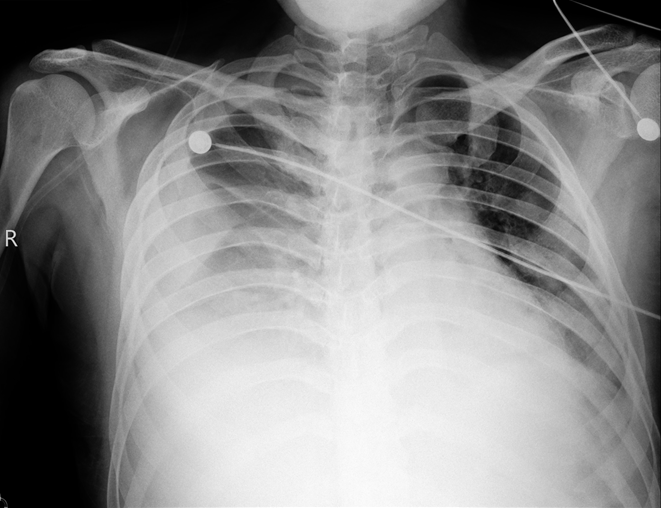

根据临床表现、影像学及肺栓塞临床评分,诊断急性肺血栓栓塞症(中高危组)明确。进一步排查深静脉血栓栓塞的易感因素,其父有肝癌病史,需进一步排查肿瘤因素,同时完善血栓调节组合、抗凝治疗监测组合等相关检查,以了解是否存在先天性抗凝因子缺乏。鉴于患者有溶栓指征,无明显溶栓禁忌证,将溶栓风险告知患者及家属,其理解并同意溶栓治疗,于2017年6月15日16:00予阿替普酶50 mg静脉持续泵入2 h溶栓治疗,溶栓时及溶栓后密切监测凝血功能变化。此外,结合患者胸部CT提示肺部有渗出,血白细胞升高,有发热、明显咳嗽、咳痰症状,考虑社区获得性肺炎(非重症),有使用抗生素指征,结合社区感染相关病原体,予左氧氟沙星0.5 g ivdrip qd经验性抗感染治疗。经上述治疗,患者仍有气促,间断咳嗽,咳少量血丝痰,2017年6月17日腹部彩超提示:①双侧少量胸腔积液;②肝静脉,汇入下腔静脉低回声,血栓形成可能;③肝、胆、脾、胰、肾、输尿管、膀胱、前列腺均未见异常。复查其凝血功能未达标,加用华法林抗凝治疗,初始剂量3 mg po qn,考虑药物需3~5 d才能达到稳定的血药浓度,为达到快速抗凝目的,使INR达到2~3,继续予低分子肝素0.8 ml H q12h重叠抗凝。同时为了解华法林量效关系,予完善CYP2C9和VK0RC1检查,通过基因多态性检测,有助于指导华法林初始剂量的选择。抗凝治疗期间多次复查凝血功能,根据结果调整抗凝药物剂量。溶栓后5 d,患者仍诉气促,呕吐频繁,反复低热,热峰不超过38℃,复查床边胸部X线片提示右侧大量胸腔积液(图2),行超声引导下胸腔穿刺置管引流术;查肝功能示转氨酶升高,予护肝治疗;加强抗感染(亚胺培南西司他丁1.0 g ivdrip q8h)。患者症状无明显好转。2017年6月20日开始频繁诉恶心呕吐,吐出胃内容物,发热,气促,活动后加重,咳嗽,咳血丝痰,无明显胸痛或胸闷不适,右侧胸腔引流管引流出血性液体。查体:神清,双上肺及左下肺呼吸音清,右下肺呼吸音明显减弱,未闻及干/湿啰音,心率111次/min,各瓣膜区未闻及病理性杂音。腹部平坦,肝右肋缘下5 cm可触及,质软,无触痛。复查出、凝血常规示:D-二聚体25.07 mg/L FEU,INR 3.19,APTT 49.7 s;ESR 56 mm/h;胸腔积液检查结果提示渗出液。取胸腔积液标本找肿瘤细胞。复查心脏彩超:下腔静脉肝后段至右心房实性回声,考虑血栓形成,估测肺动脉压28 mmHg(图3)。考虑恶心呕吐与肝静脉血栓形成、肝淤血致肝功能异常相关,停用可能导致肝损害的药物,继续抗凝,加强护肝、退黄、平喘治疗及营养支持。经上述治疗,患者气促情况有好转,但肝功能损害加重,肝酶、胆红素及血氨水平进行性升高,凝血功能明显异常,ALT 1819 U/L,AST 6345 U/L,LDH 5860 U/L,TBIL 70.8 μmol/L,DBIL 27.6 μmol/L,IBIL 43.2 μmol/L,维持护肝、降血氨治疗,及时纠正非预期凝血功能障碍,复查胸+上腹+下腹CTA平扫+增强+三维,查风湿组合Ⅰ+Ⅱ,自身免疫性肝病组合,抗磷脂综合征组合等相关检查,帮助明确肺血栓情况,查找肝功能进行性异常的原因,风湿免疫相关检查结果无异常。2017年6月22日行CTA示:①肺动脉主干,左、右肺动脉干,左上、下肺动脉及其分支,右下肺动脉主干及外基底段近段肺动脉栓塞,左下肺动脉栓塞较前范围稍扩大,右下肺动脉病变范围较前稍减轻;下腔静脉近右心房至肝段上部、下腔静脉肾静脉水平—双侧髂总静脉—双侧髂外静脉及肝左、中、右静脉管腔多发血栓形成,较前进展。②肺部炎症、胸腔积液。③心包积液较前稍增多,腹腔、盆腔少量积液(图4)。注:A:右心房血栓;B:下腔静脉延续到右心房处血栓,肝静脉未显影;C:CTA示下腔静脉近右心房端、肝静脉多发血栓形成;D:CTA另一层面示下腔静脉血栓,肝内静脉未显影,考虑栓塞;E、F:复查胸部CTA示肺动脉主干栓塞6月22日夜间患者出现谵妄、躁动不安,不能正确应答,查血氨升至191 mmol/L(图5)。考虑患者多部位静脉血栓形成,肝静脉栓塞,肝脏淤血明显,已并发肝性脑病,有急性肝衰竭可能,予乳果糖口服溶液灌肠,门冬氨酸鸟氨酸降血氨治疗,患者解出大便后症状稍好转,密切观察肝功能变化情况。请院内多学科会诊,多学科意见考虑患者目前存在多部位静脉血栓,急性肝损伤,凝血功能严重异常,手术风险极大,不建议行手术取栓治疗,建议继续内科药物治疗,可考虑行二次系统溶栓。与患者及家属沟通病情并取得知情同意后,2017年6月25日行第二次溶栓,予阿替普酶50 mg静脉持续泵入2 h,同时密切观察全身出血情况,预防出血,继续对症支持治疗。患者意识障碍加重,尿少,出现肝肾综合征,凝血功能异常。床边腹部超声:①右肝静脉血栓形成、闭塞,中肝静脉第二肝门处血栓形成,血流通畅,双向血流;②下腔静脉血栓形成,彩色多普勒血流成像(CDFI)探查不佳;③左肝静脉双向血流;④肝动脉、门静脉血流通畅。当天患者意识障碍进一步加重,昏迷状,呼吸衰竭,行气管插管接呼吸机辅助通气,气道内吸出血性分泌物,多次复查结果示肝功能及凝血功能严重异常,低纤维蛋白原血症,考虑存在肝静脉、下腔静脉血栓相关的布加综合征。请血液科会诊,考虑低纤维蛋白原血症系由肝损、溶栓药物、DIC消耗等多因素引起,建议完善凝血因子监测,根据结果及INR补充新鲜冰冻血浆、凝血酶原复合物、维生素K1等。患者因少尿,行床边连续性肾脏替代治疗(CRRT),体外肝素化抗凝,但因滤器及管路凝血而提前结束治疗。请感染科会诊,建议继续予护肝、降酶、退黄治疗,补充血浆及白蛋白,加强肺部及腹部抗感染治疗。请血管外科会诊协助处理肝静脉血栓,血管外科建议考虑下腔静脉、肝静脉机械取栓或置管溶栓,辅以全身肝素化抗凝,以改善肝脏血流,但因手术风险极高,家属不愿行取栓/溶栓术。虽给予积极药物治疗,患者肝功能改善情况不理想,凝血功能差,反复输注血制品情况下出现顽固性低纤维蛋白原血症,合并全身散在部位出血,预后差,2017年6月30日家属办理自动出院手续。| 该患者入院时无明显血流动力学不稳表现,影像学显示双肺动脉栓塞较严重,存在肺动脉骑跨,发病早期即发现肝静脉、下腔静脉多发血栓形成,入院后1周内出现肝衰竭,病程进展迅速。针对该患者的治疗难点有哪些?回顾这一病例,是否有更有效的方法进行治疗? |